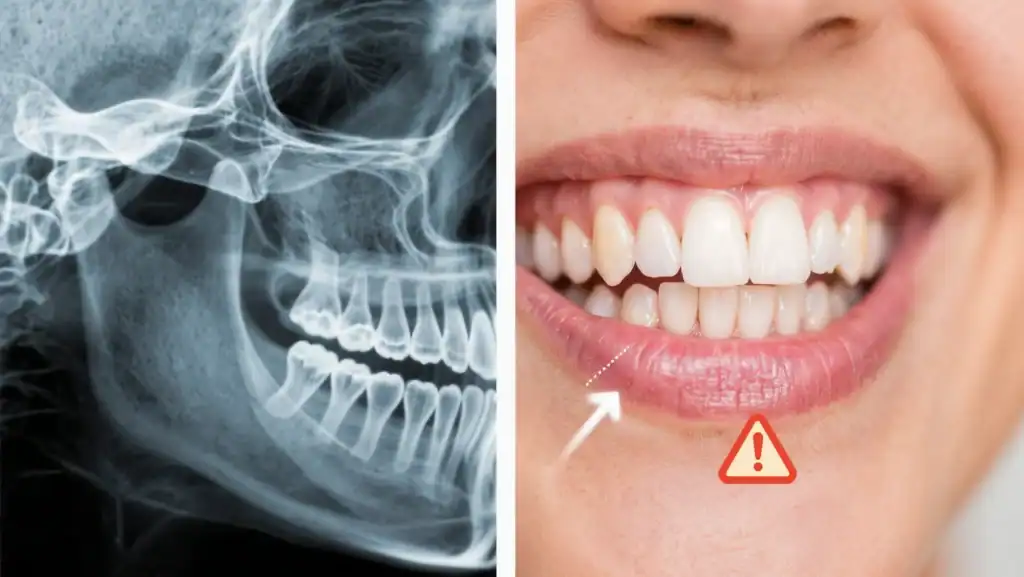

Your maxillary sinuses—the air-filled cavities located above your upper back teeth—share an intimate relationship with your dental health. These sinuses are separated from your tooth roots by only a thin layer of bone. When you lose upper back teeth, something remarkable and problematic happens: your sinus cavity begins to expand downward while the supporting bone simultaneously shrinks away.

This natural process, called pneumatization, creates a double challenge for dental implant placement. The expanding sinus leaves insufficient bone height for implant stability, while bone resorption reduces the foundation needed for long-term success. Without adequate bone support, implants in the upper jaw face significantly higher failure rates.

Sinus augmentation, commonly known as a sinus lift, represents one of the most predictable and successful procedures in modern implant dentistry. This sophisticated technique involves carefully lifting the sinus membrane and placing bone grafting material in the newly created space beneath it. The result? A solid foundation of regenerated bone that can securely support dental implants for decades.